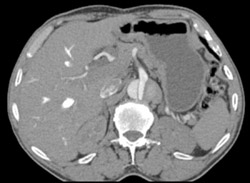

Active Bleed Following Arterial Puncture